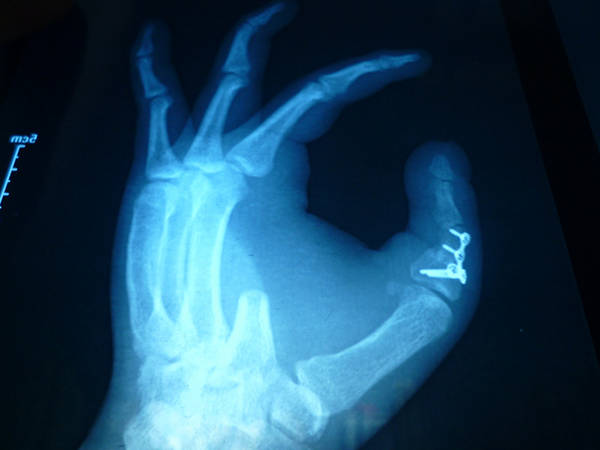

[手指再造] 拇再造术后供区的另一种修复(12.23随访照片来了)

池老师手术做的确实漂亮。有个疑问:既然食指切除了,为何不直接把废弃食指指骨连同食指皮瓣修复再造供区,这样就不用取游离腓骨皮瓣了

1.jpg 2.jpg 3.jpg 4.jpg 5.jpg 6.jpg 7.jpg 8.jpg 9.jpg 10.jpg 11.jpg 12.jpg 13.jpg

功能和外观都很好,学习了,池主任的病人应该感到幸运和幸福